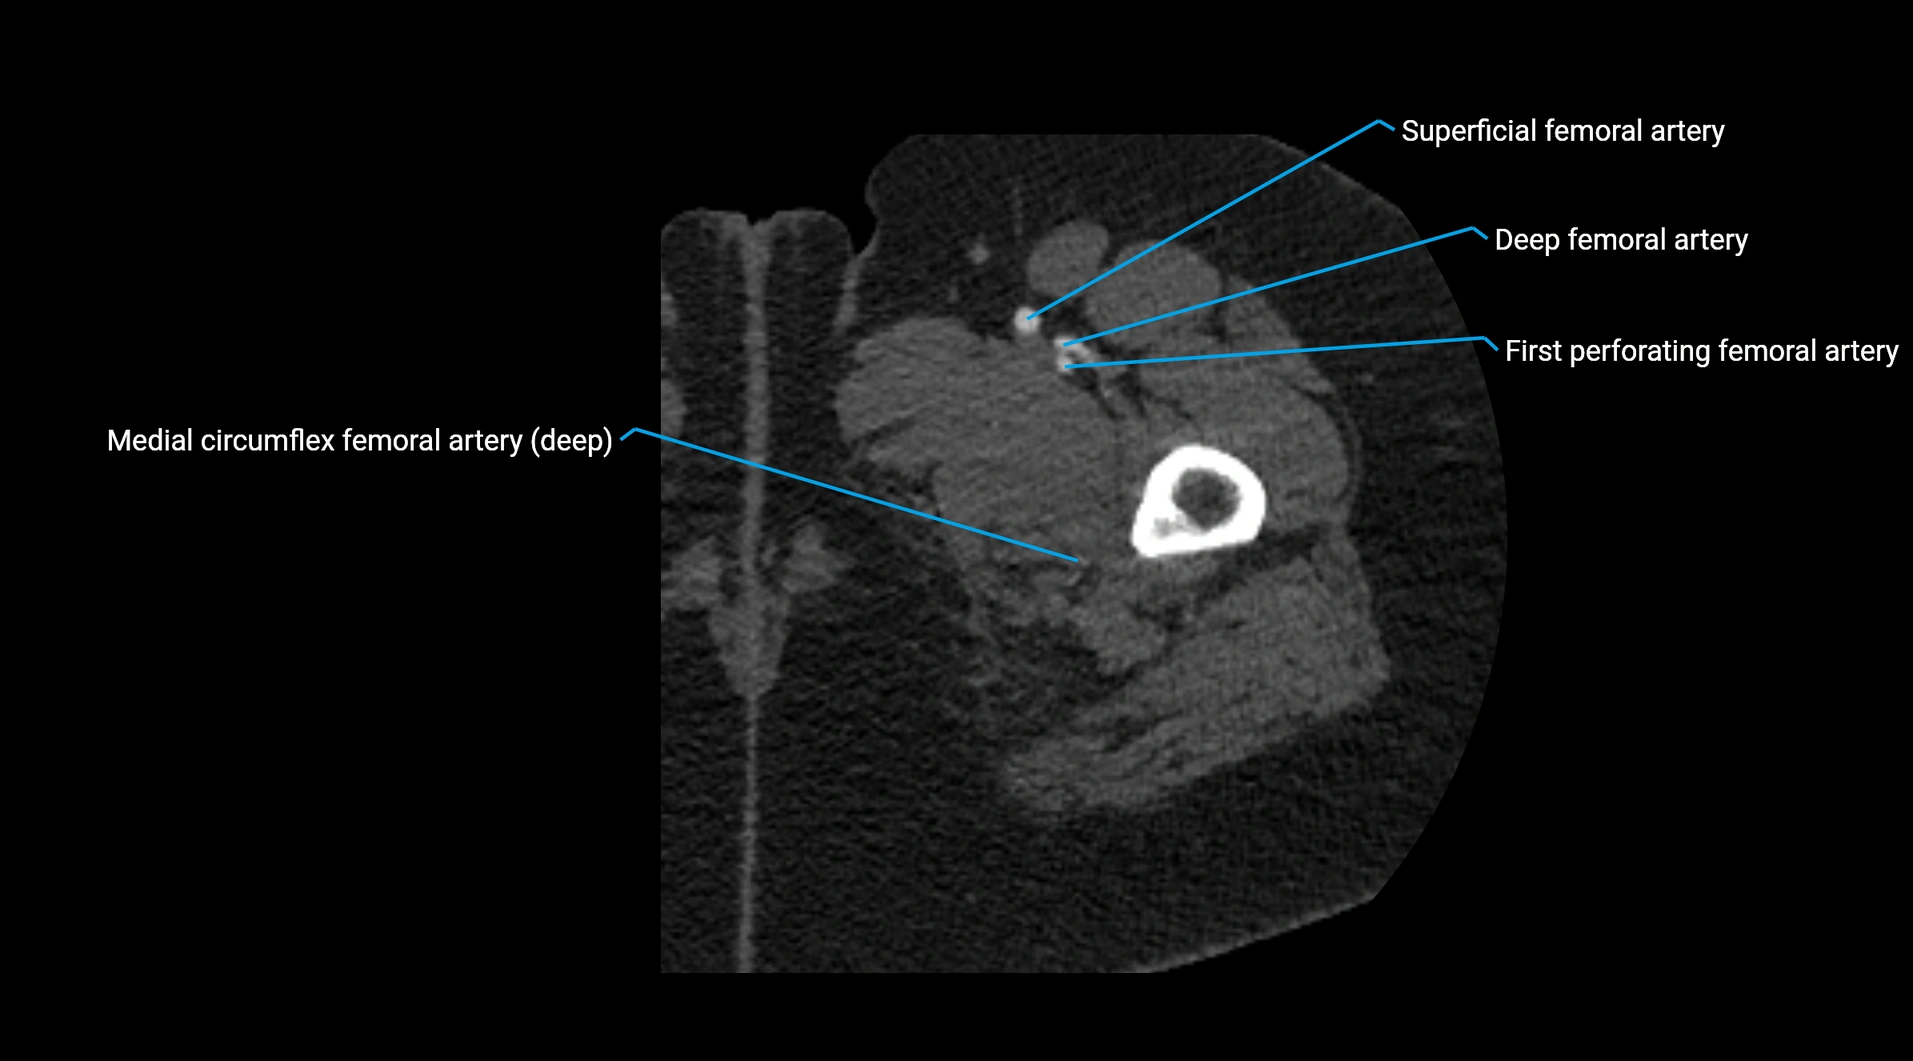

CT Appearance

Non-contrast CT:

• Appears as a tubular soft tissue structure anterior to vertebral bodies

• Calcified atherosclerotic plaques appear as hyperdense foci along the wall

• Useful for screening abdominal aortic aneurysm (AAA) size and mural calcification

Contrast-enhanced CT (CTA):

• Gold standard for abdominal aortic imaging

• Provides excellent detail of lumen, wall, aneurysm, thrombus, and branch vessels

• Multiplanar and 3D reconstructions help in aneurysm measurement, stent graft planning, and dissection evaluation

• Detects acute rupture, traumatic injury, or occlusion with high sensitivity